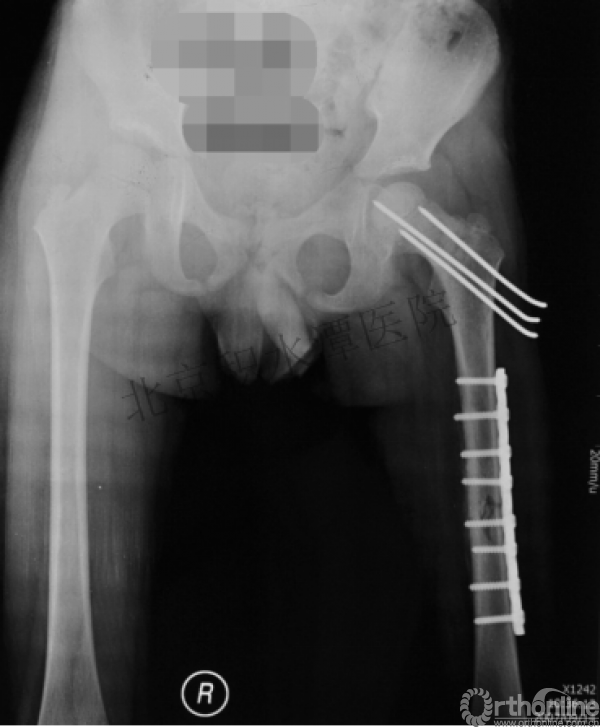

钢板固定后一年

取板后再骨折→TEN

TEN取出后2个月

闭合复位再固定加尾帽